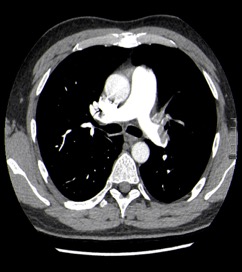

Nuestro paciente tiene síntomas respiratorios y un valor elevado de Dímero D. El Angio-TC nos permite hacer una valoración más detallada del estado de la anatomía vascular pulmonar así como del del corazón: También nos va a proporcionar una visión más en detalle del parénquima pulmonar.